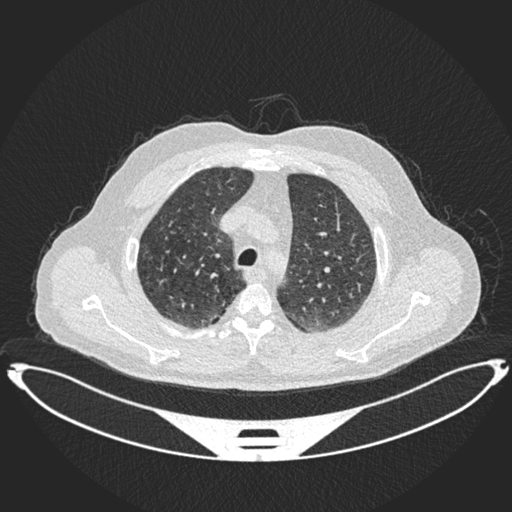

Analyzed Image

a.jpg

Uploaded: 2025-08-03 04:59:46Best Model Result

Normal

Confidence: 57.5%

Model: DenseNet121

Ensemble Prediction

Confidence: 39.5%

Average of all modelsModel Predictions Comparison

ResNet50

Malignant

Bengin:

32.1%

Malignant:

34.5%

Normal:

33.3%

ConfidenceDenseNet121

31.6%

10.8%

57.5%

ConfidenceEnhancedCNN

19.7%

52.6%

27.7%